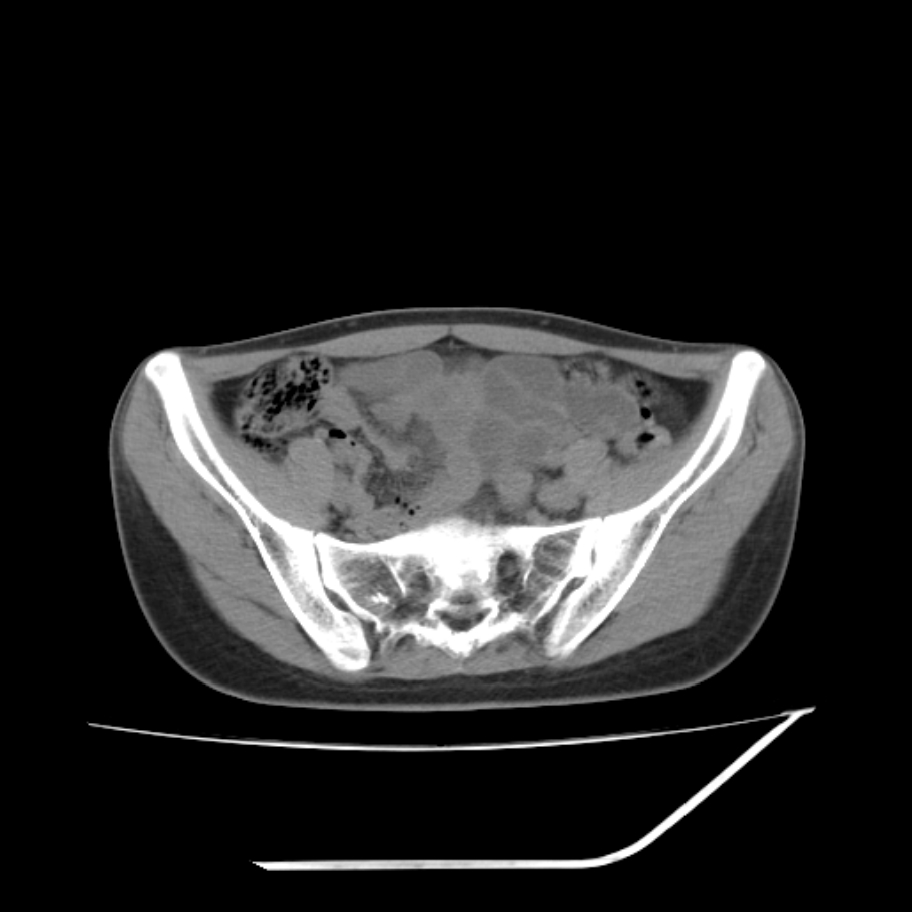

女,25岁。偶尔有右下腹不适感,余无明显异常。(结婚半年),囊壁较厚,是卵巢囊肿吗?

其上一层面见两枚小气泡影,考虑为肠管影可能,不完全除外囊肿

右侧卵巢区椭圆形囊性肿物,内壁光滑 无分隔。直肠子宫间隙内有少量积液征象。结合临床考虑卵巢巧克力囊肿,还要问问有没有痛经,本例ct怎么没有灌肠?要是灌肠或前一前口服造影剂,起码可以和肠管区别开

b超示:囊实性占位,畸胎瘤?临床有痛经。

考虑右侧卵巢囊性占位性病变(巧克力囊肿?),盆腔积液有不排除宫外孕可能,请结合临床和b超。

右侧卵巢囊伴盆腔少量积液。